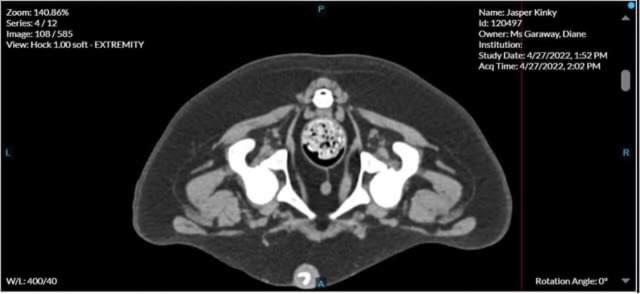

• Scan of Jaspers hips

Main image

Poor Japsers hips, hence why he struggles to keep up with his friends 😢😢

• Jasper’s CT scan results - update from Diane

His hips have quite bad dysplasia and will require surgery, possibly hip replacement.